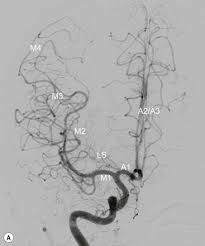

모야모야병은 일본어인 もやもや 에서 유래되었다. 모야모야는 연기가 피어오르는 모양을 나타내는 일본어인데, 실제 모야모야 병에서 뇌혈관의 모양은 마치 연기가 피어오르는 것처럼 보인다.

위에 우측 사진에서 보이는 것처럼 뇌혈관의 모양은 양갈래를 뻗은 나무줄기처럼 생겼다. 하지만 모야모야 병 환자의 경우 좌측의 사진과 같이 뇌혈관이 굵은 줄기가 없이 무수히 많은 잔가지만을 낸 것처럼 보인다. 이러한 병적인 혈관들을 모야모야 혈관이라고 부른다. 당연하지만 이러한 모야모야 혈관들은 정상 혈관에 비하여 매우 약하다.